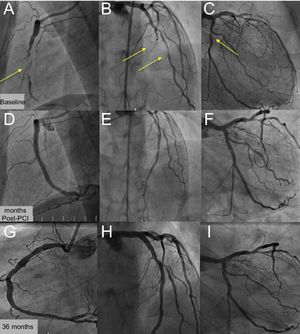

We present the case of a 36-year-old woman with familial dyslipidemia, a positive ischemia induction test and multivessel coronary artery disease, chronic occlusion of the right coronary artery and left anterior descending artery, with lesions in the diagonal branch and circumflex artery (Figure 1A-C, yellow arrows). The patient was entered in the ABSORB-CTO study and underwent complete percutaneous coronary intervention (PCI) with 8 bioresorbable vascular scaffolds (BVS): 4 in the right coronary artery (Figure 1D and Figure 2A), 2 in the left anterior descending artery (Figure 1E and Figure 2D), 1 in the diagonal branch and 1 in the circumflex artery (Figure 1F). Optical coherence tomography was also performed after the procedure and at 12 and 36 months. Dual antiplatelet therapy was continued for 3 years. At 12 months, the struts of the right coronary artery and left anterior descending artery were endothelialized (Figure 2B and E, yellow arrows), well apposed, and had more intimal hyperplasia in the overlap area (Figure 2B and E, red arrows). At 36 months, all segments remained free from restenosis (Figure 1G-I) and optical coherence tomography showed resorption of the struts (Figure 2C and F, yellow arrows), with dissolved black boxes, including the area of overlap (Figure 2C and F, red arrows).

This case of a young woman with multivessel coronary disease and complete percutaneous revascularization with 8 BVS (194mm scaffold) shows the excellent long-term outcome with resorption of the scaffolds.